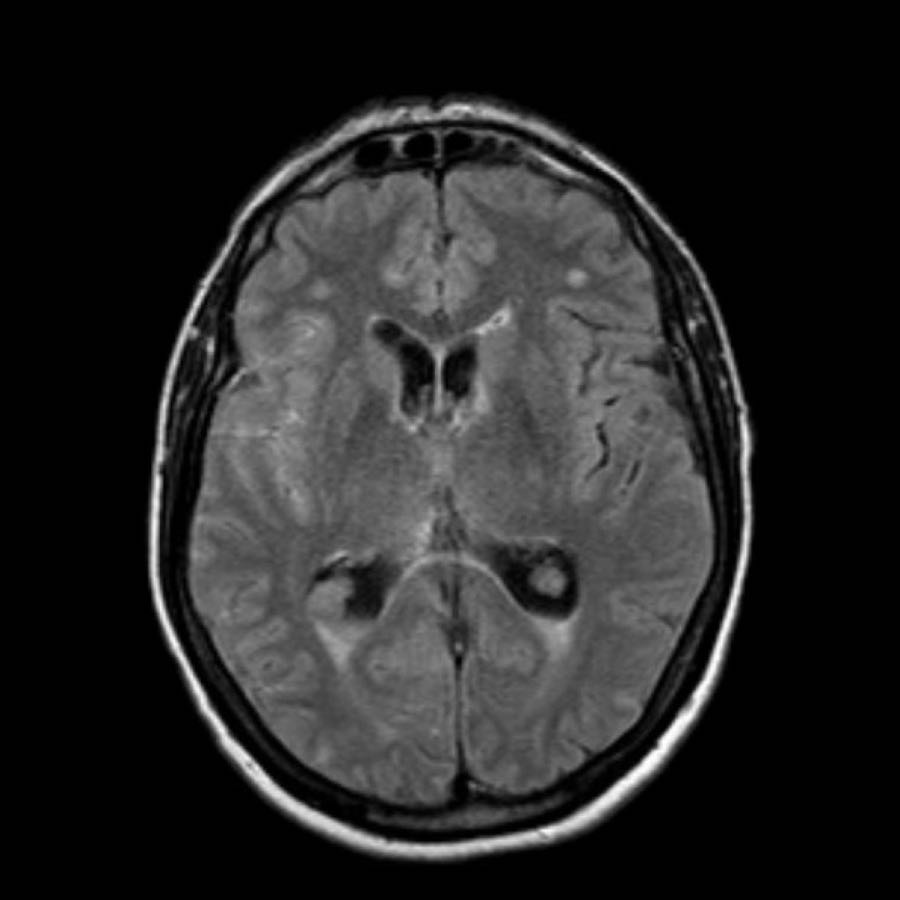

Đây là một ví dụ về xuất huyết dưới nhện trên NECT.

Lưu ý vị trí máu chủ yếu xung quanh thân não và trong não thất III và IV.

Thông thường, vị trí của máu dưới nhện giúp định hướng xác định vị trí của túi phình động mạch.

Bước tiếp theo là thực hiện chụp CT mạch máu (CTA) để tìm kiếm túi phình động mạch là nguyên nhân gây SAH.

Bệnh nhân này có túi phình tại nguyên ủy của động mạch tiểu não sau dưới trái (PICA).

Cũng cần lưu ý tình trạng não úng thủy.